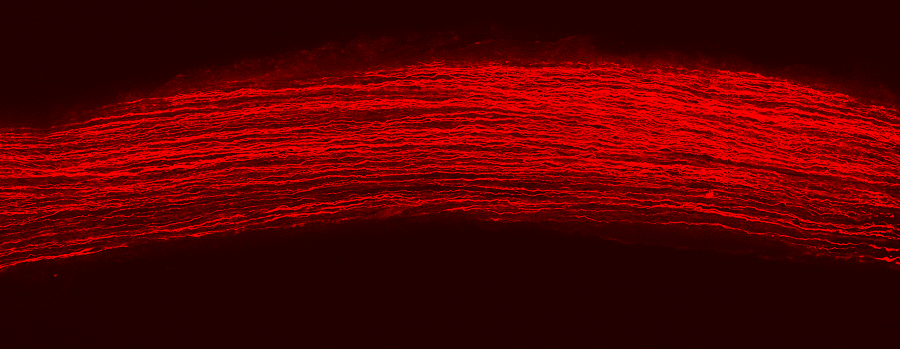

图注:(上)CasRx通过靶向的降解Ptbp1 mRNA从而实现Ptbp1基因表达的下调。(中)视网膜下注射AAV-GFAP-CasRx-Ptbp1可以特异性的将视网膜穆勒胶质细胞转分化为视神经节细胞,转分化而来视神经节细胞可以和正确的脑区建立功能性的联系,并且提高永久性视力损伤模型小鼠的视力。(下)在纹状体中注射AAV-GFAP-CasRx-Ptbp1可以特异性的将星形胶质细胞转分化为多巴胺神经元,从而基本消除了帕金森疾病模型小鼠的运动症状。

视神经部位是连接眼睛和大脑的桥梁。每一条红色的线是每一个再生出来的视神经节细胞发出的轴突,通过这里,这些新生轴突将会与大脑中处理视觉信号的区域正确相连。